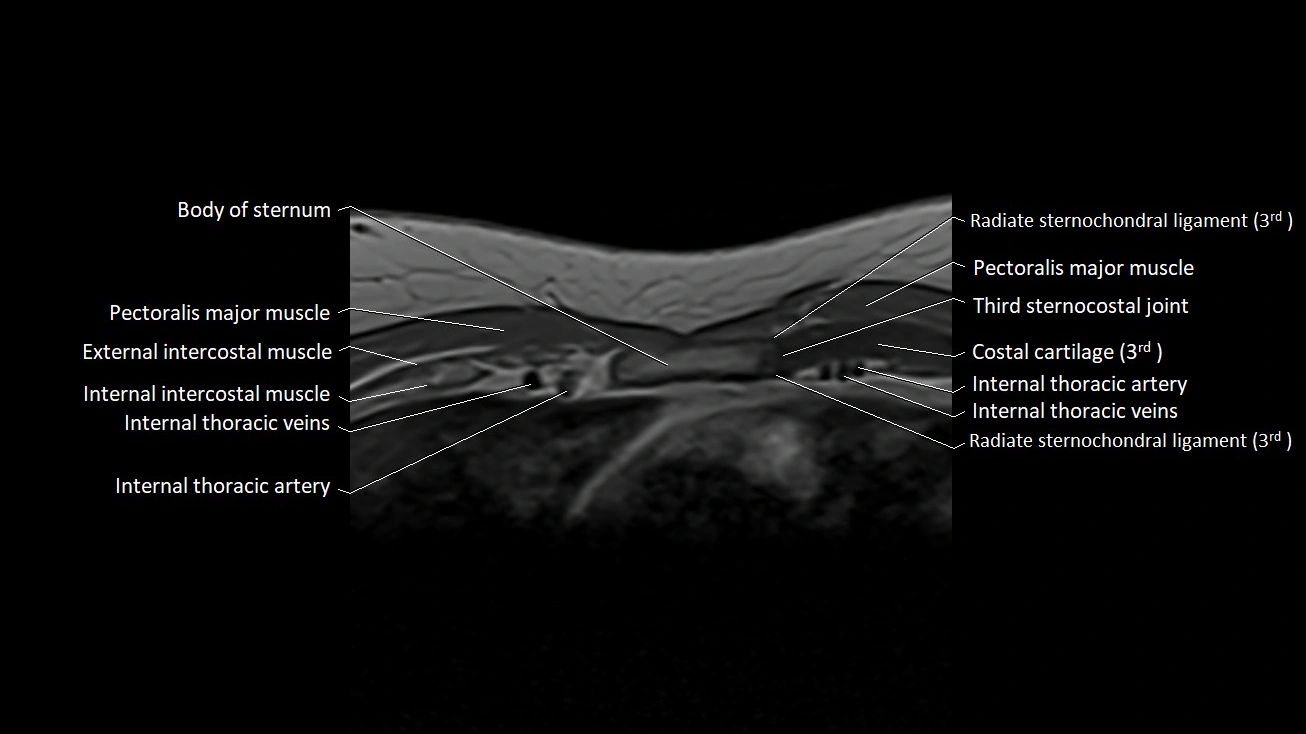

MRI images

image